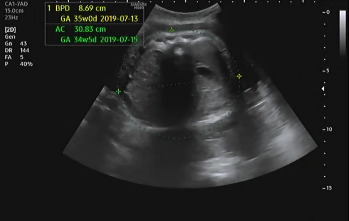

진료 순서가 되어 복부 초음파를 확인하였다. 여전히 햇님이는 자신의 건강함을 알리기 위해 초음파를 보는 내내 손을 이리저리 움직였다. 머리둘레, 복부둘레, 허벅지 뼈 길이를 측정하여 대략적인 체중을 확인하고 태아가 주수에 알맞게 크고 있는지를 확인했다. 머리둘레는 35주 차, 복부둘레는 34주 5일, 허벅지 뼈 길이는 33주 4일이라서 이상하다 생각했는데 평균적 수치는 주수에 알맞게 성장이라는 것을 듣고 안심했다. 2주 뒤인 37주 차에 내원을 예약했다.